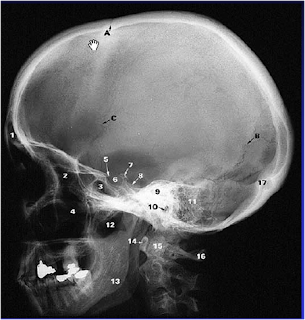

Kriteria Gambaran :

1. MAE

2. TMJ

3. Sinus Frontalis

4.Sinus Maxillaris

5. Mandibula

6. Ramus Mandibula

7. Sphenoid

8. Mastoid air cells

9. Sella tursica.

10. Oss Temporal

11. Oss Frontal

12. Oss Parietal.

13. Oss Occipital

14. Oss Nasal

14.Oss Maxilla

15. Suture Coronalis

16.Suture Lambdoidea

17. Vertebra Cervical.

Tujuan Posisi Lateral adalah untuk melihat bagian dari Kepala dengan posisi dari samping untuk melihat TMJ dan MAE.